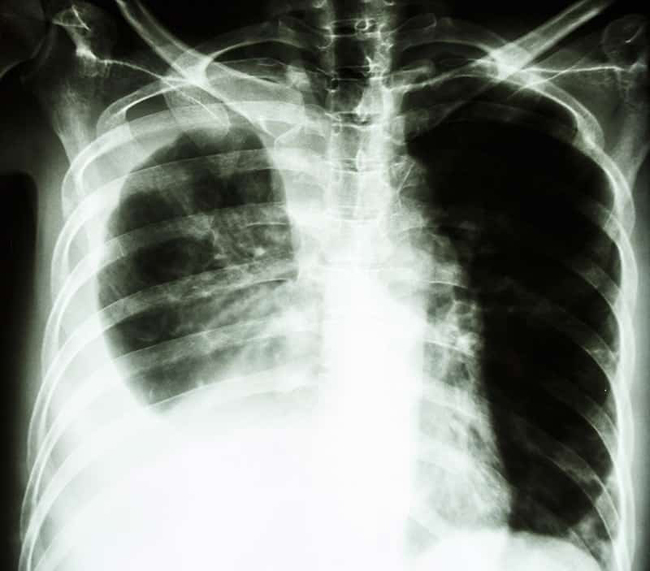

Phát hiện và điều trị bệnh lao sớm sẽ tránh được những biến chứng nguy hiểm. Ảnh minh họa